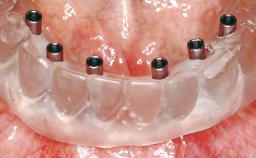

Immediate Loading of Eight Implants in the Maxilla and Six Implants in the Mandible and Final Restoration with Three-Unit and Four-Unit FDPs

Extensive scientific evidence has confirmed that immediately loaded implants with fixed full-arch provisional restorations can osseointegrate with success rates similar to conventionally or delayed loaded implants. A number of immediate-provisionalization techniques for edentulous jaws have been described. Some protocols differ when it comes to prefabricated provisional templates versus complete denture conversion; intrasurgical impressions versus direct relining; and cemented versus screw-retained provisional restorations. In this context, complete-denture conversion has been proposed for either intrasurgical impressions or direct relining. Another possibility is the utilization of a prefabricated provisional to be adapted either in the mouth (by direct relining) or in the laboratory (on a working model obtained from an intrasurgical impression).

Loading Protocol Immediate

Provisional Implant-Supported Prosthesis Prosthodontic margin < 3 mm apical to mucosal crest Prosthodontic margin < 3 mm apical to mucosal crest